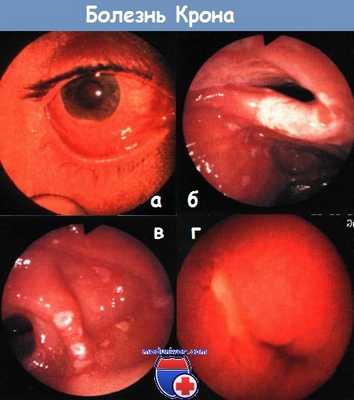

а - ирит при болезни Крона. Выраженная конъюнктивальная инфекция, гипопион.

б - терминальный илеит при болезни Крона. Илеоскопия при колоноскопии.

в - рецидив болезни Крона после резекции: поражена оставшаяся часть терминального отрезка подвздошной кишки.

г - язвы в тощей кишке при болезни Крона. Капсульная эндоскопия.